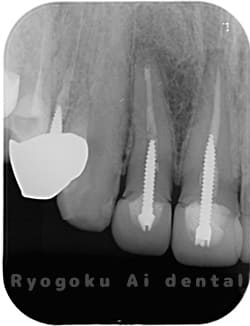

Case02

- 原因

- 慢性根尖性歯周炎

- 治療期間

- 1回(消毒・洗浄も含めると3回)

- 治療内容

- 歯根端切除術

- 治療費用

- ¥110,000

他院で抜歯と判断され、インプラント治療を提案された患者様です。被せ物を外さずに、歯の根尖部に外科的にアプローチし、病気の部分を除去しました。

<リスク・副作用>

外科手術のため、術後に出血、痛みや腫れ、違和感を伴います。口腔内の状態によっては適応できないことがあります。歯根端切除で治らなければ抜歯を検討しなくていけない場合もあります。